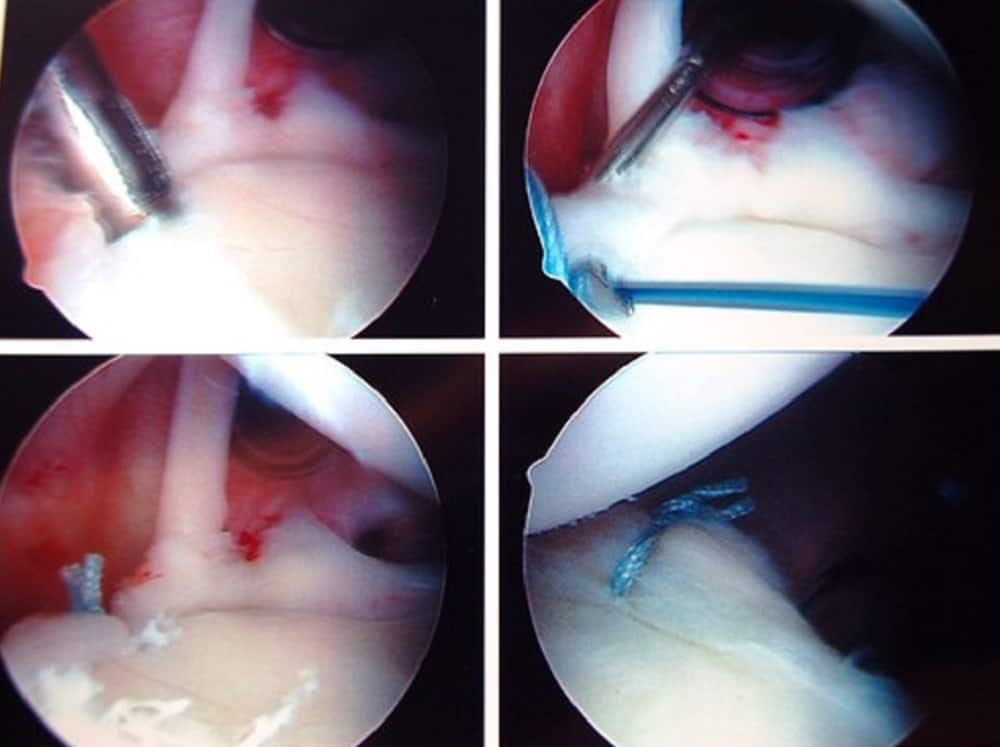

ऑपरेशन शुरू करने से पहले बेहोश या सुन्न करने की प्रक्रिया की जाती है। शोल्डर सर्जरी को करने में लगभग 45 मिनट का समय लगता है। शोल्डर सर्जरी के लिए ऑरथ्रोस्कोपी का इस्तेमाल किया जाता है। जिसमें सबसे पहले एक चीरा या कट लगाया जाता है। फिर सर्जरी के दौरान सर्जन उपकरणों की मदद से मोटे टिशू या हड्डी के कुछ हिस्से को निकाल दिया जाता है। इसके बाद सर्जन रोटेटर कफ को रिपेयर करना शुरू करता है। इसके लिए ज्यादातर सर्जन कीहोल सर्जरी (keyhole surgery) को अपनाते हैं। इसके बाद सर्जन हड्डियों के साथ मांसपेशियों को सिलते हुए टांका लगाया जाता है।